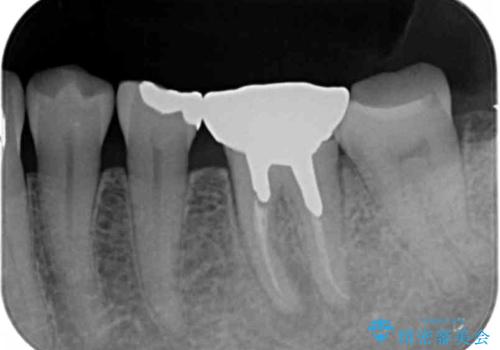

X線写真より根の先に病変が認められたため、根管治療を行ったのちジルコニアクラウンによる咬合機能回復治療を計画します。